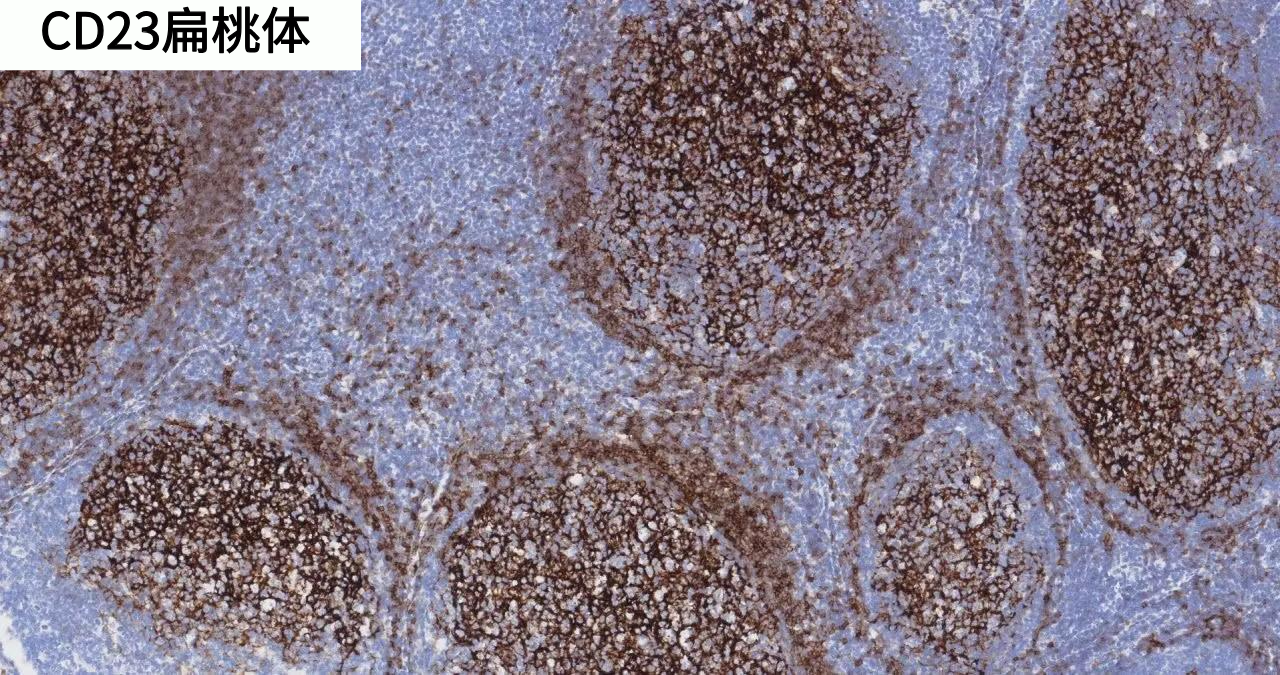

CD23 | ZM-0273 | UMAB101 | 細(xì)胞膜 | 扁桃體/濾泡性淋巴瘤 |

產(chǎn)品染色圖賞析